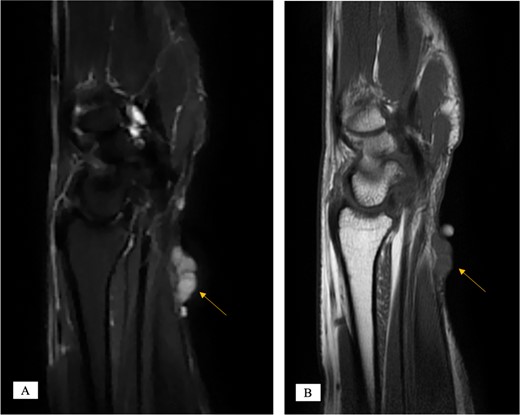

X-ray showed a well-defined non-aggressive lytic bony lesion of the first metacarpal bone (Fig. 1). Magnetic resonance imaging (MRI) showed a grossly stable skin and subcutaneous multilobulated soft tissue mass located at the palmar aspect of the wrist joint measuring 6 × 2 × 3.3 cm3 in its maximum anteroposterior, transverse and craniocaudal dimensions, respectively (Figs 2 and 3). The lesion showed low and high signals in T1 - and T2-weighted images with homogenous contrast enhancement. The lesion was inseparable from the flexor carpi radialis and palmaris longus tendons without definite invasion or encasement. The lesion was not in continuity, however, with the serpiginous lytic bony lesion noted at the first metacarpal bone exhibiting low T1 and high T2 signals with peripheral enhancement and no cortical destruction or associated soft tissue component (Fig. 4).

MRI of the left distal forearm showing cutaneous and subcutaneous lobulated mass at the volar aspect of high T2 and low T1 signals with diffuse enhancement. (A) Coronal T2-weighted fat saturated image. (B) Axial T2-weighted fat saturated image. (C) Axial T1-weighted image. (D) Axial T1-weighted fat saturated image post gadolinium injection.

MRI of the left distal forearm showing cutaneous and subcutaneous lobulated mass at the volar aspect of high T2 and low T1 signals with diffuse enhancement. (A) Sagittal T2-weighted fat saturated image. (B) Sagittal T1-weighted image.